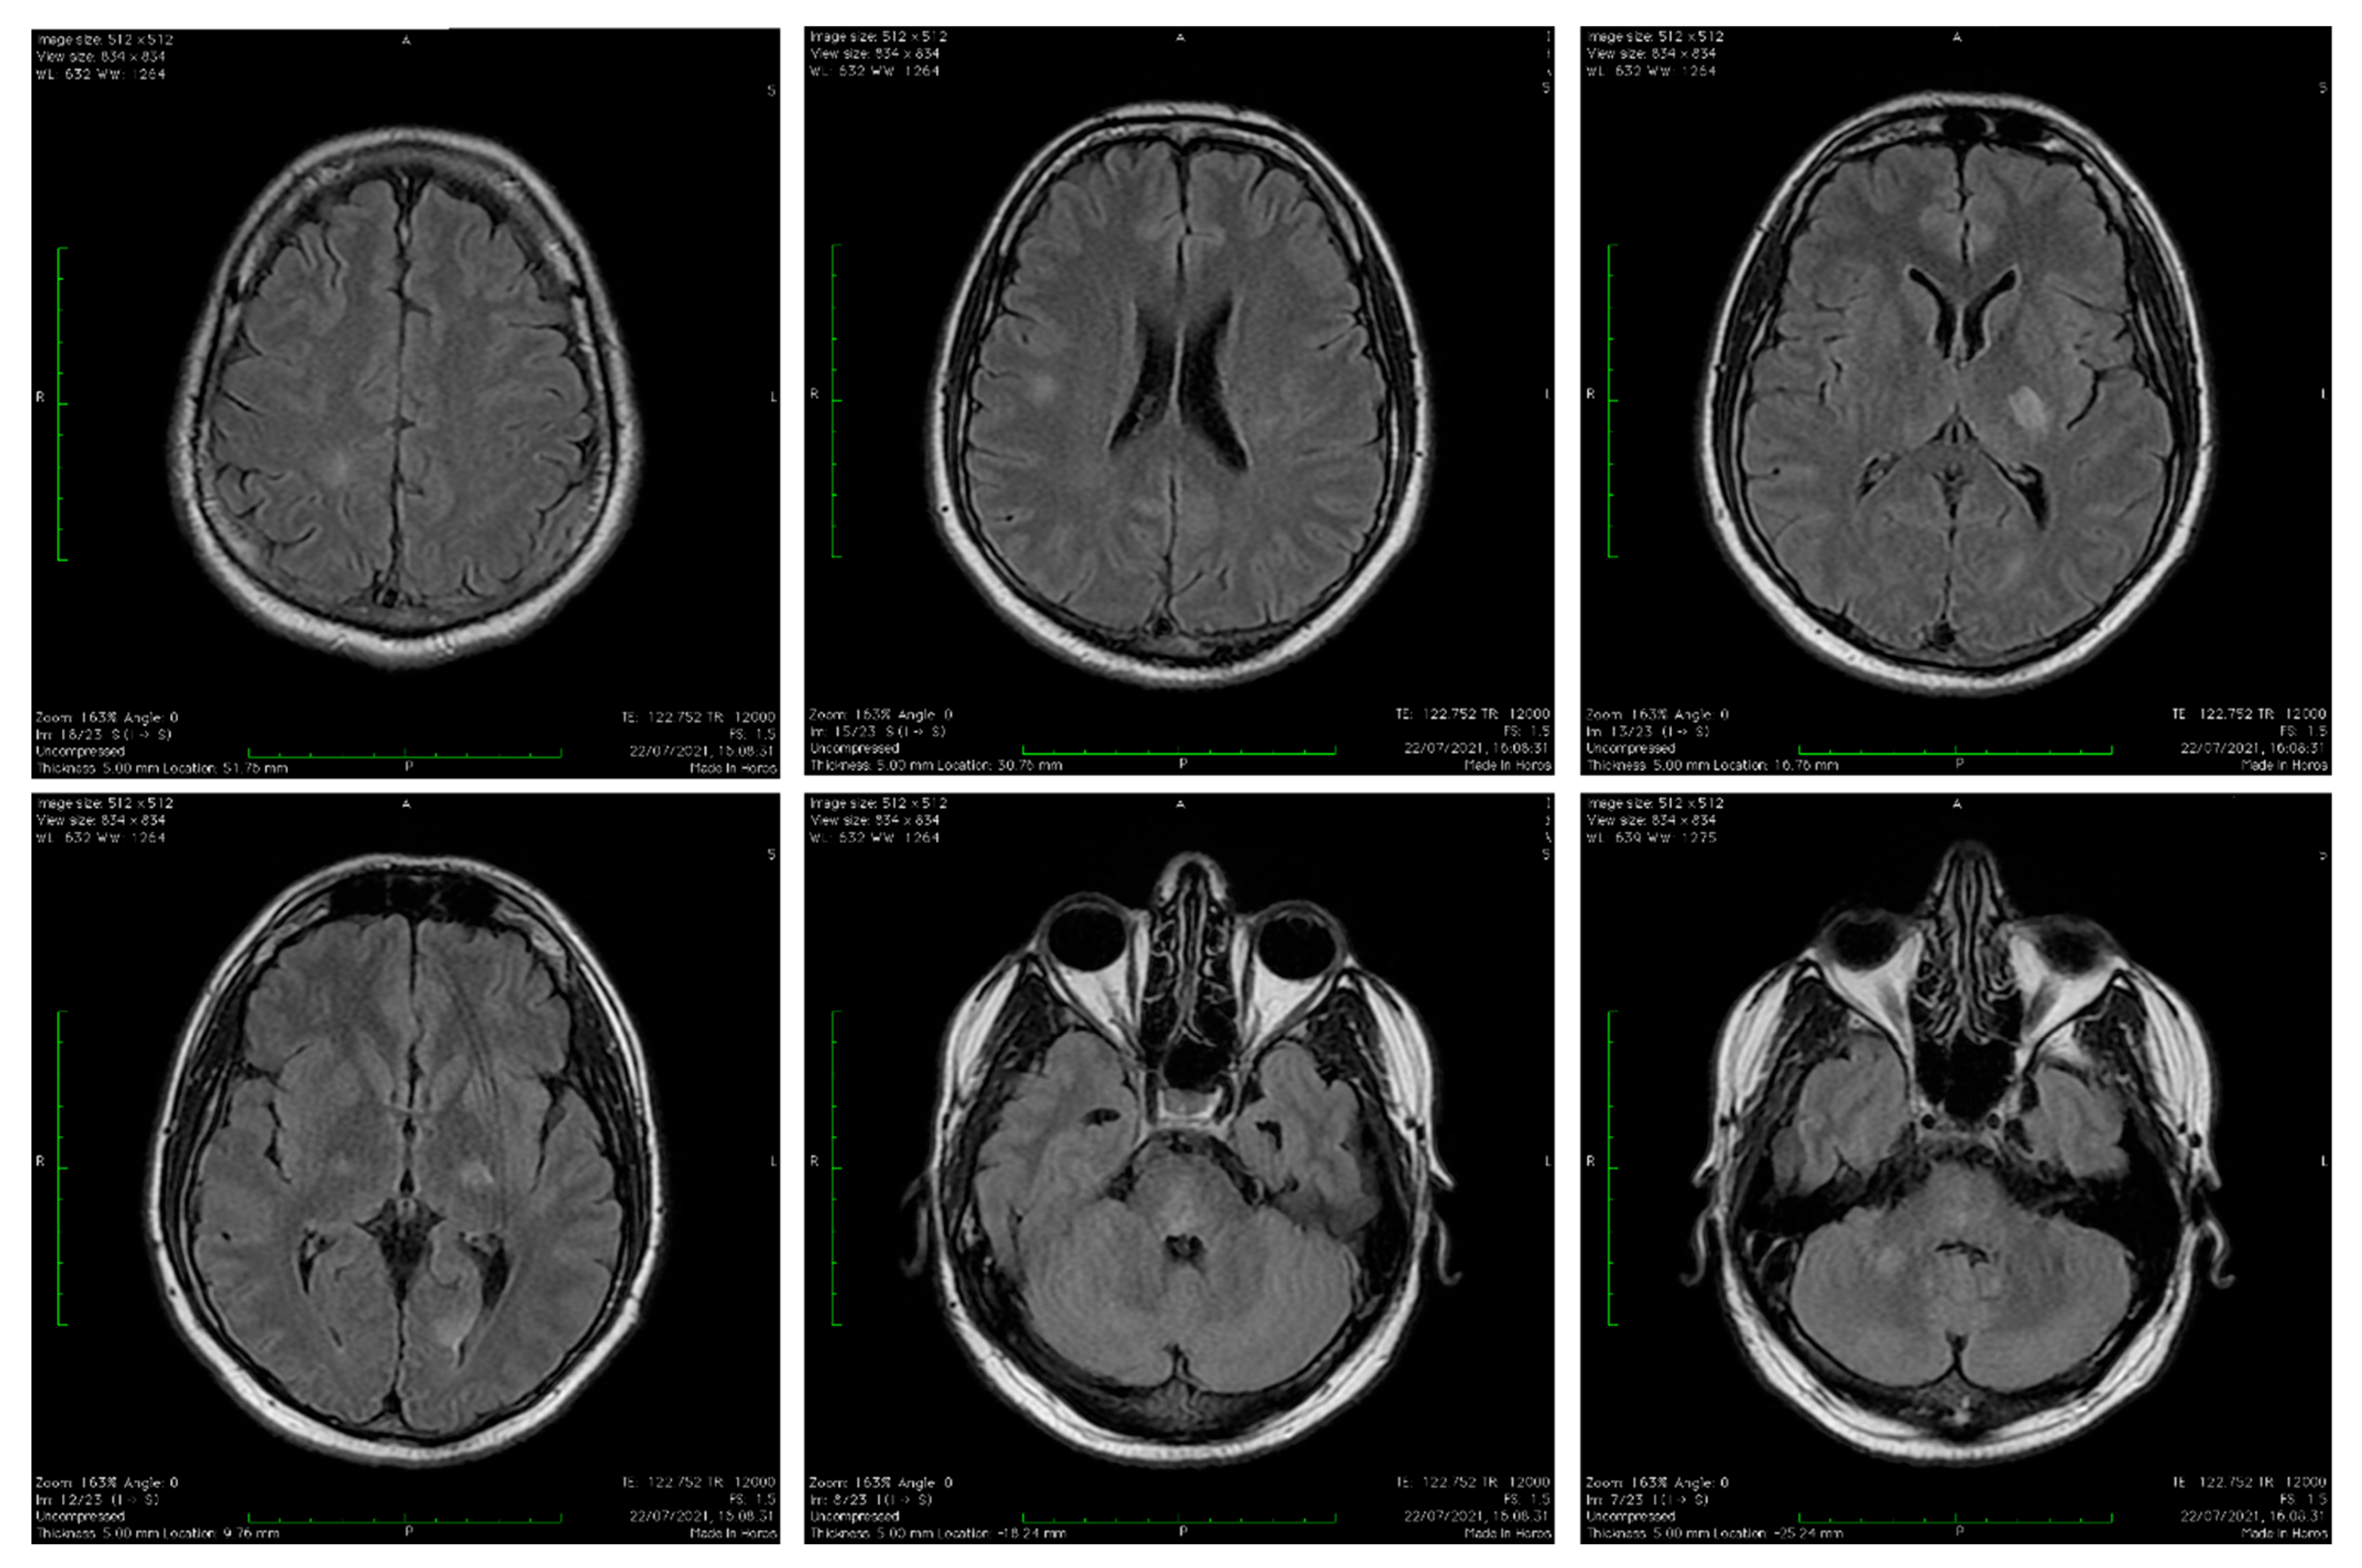

3.1. Our Clinical Experience

- Appearance on MRI images;

- Brain and/or spine MRI shows lesions in the acute phase (3 months).

- Brain lesions on MRI are diffuse and poorly demarcated and have the following characteristics:

- Large-size lesions of 1–2 cm that mainly affect the white matter.

- Hypointense T1 lesions affecting white matter are rare.